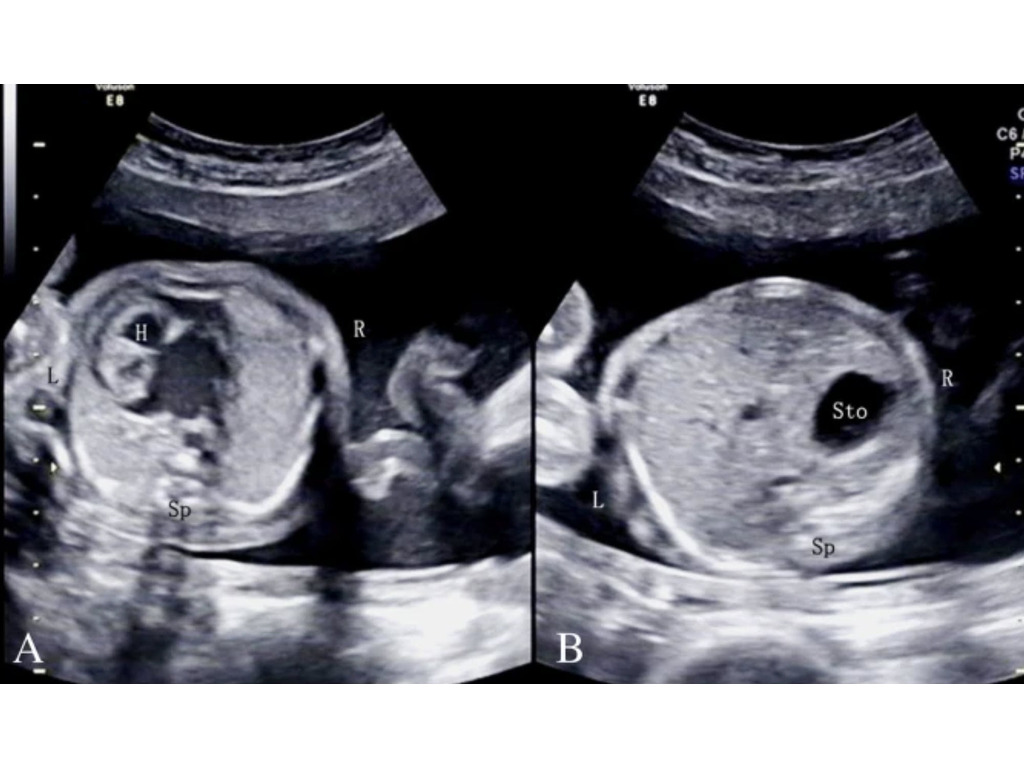

What is the feral lie based on the anatomy showed?

Vertex spine up

Breech spine down

Breech spine up

Vertex spine down